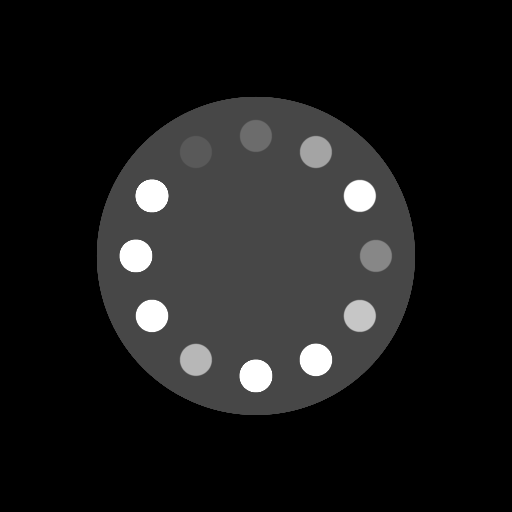

Ground-truth References

(20-cm cylindrical phantom)